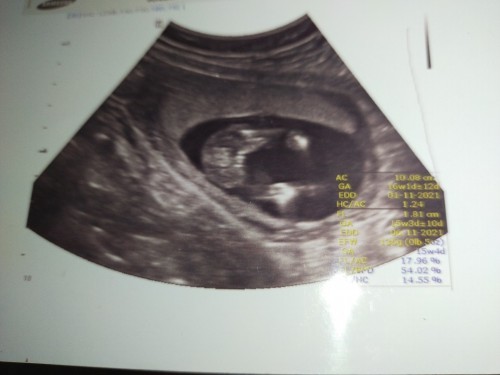

แม่ๆช่วยดูหน่อยค่ะว่าน้องผู้ชายหรือผู้หญิง ตอนซาวหมอไม่บอกอะไรเรื่องเพศเลย ตอนไปซาว16วิคค่ะ

บอกไม่ถูกเหมือนกันค่ะ ขนาดคุณหมอยังไม่บอกเลย 😁 คิดว่าคุณหมออาจจะยังไม่แน่ใจ

น่าจะ ผญ นะคะ ของเรา17 วีค ผช คะ จะประมาณนี้คะ

น่าจะผญนะคะ แบบมีแคม3กลีบ

ไม่มีจู๋ โผล่ หญิงค่ะ

น่าจะผู้หญิงค่ะแม่

น่าจะผู้หญิงนะคะ